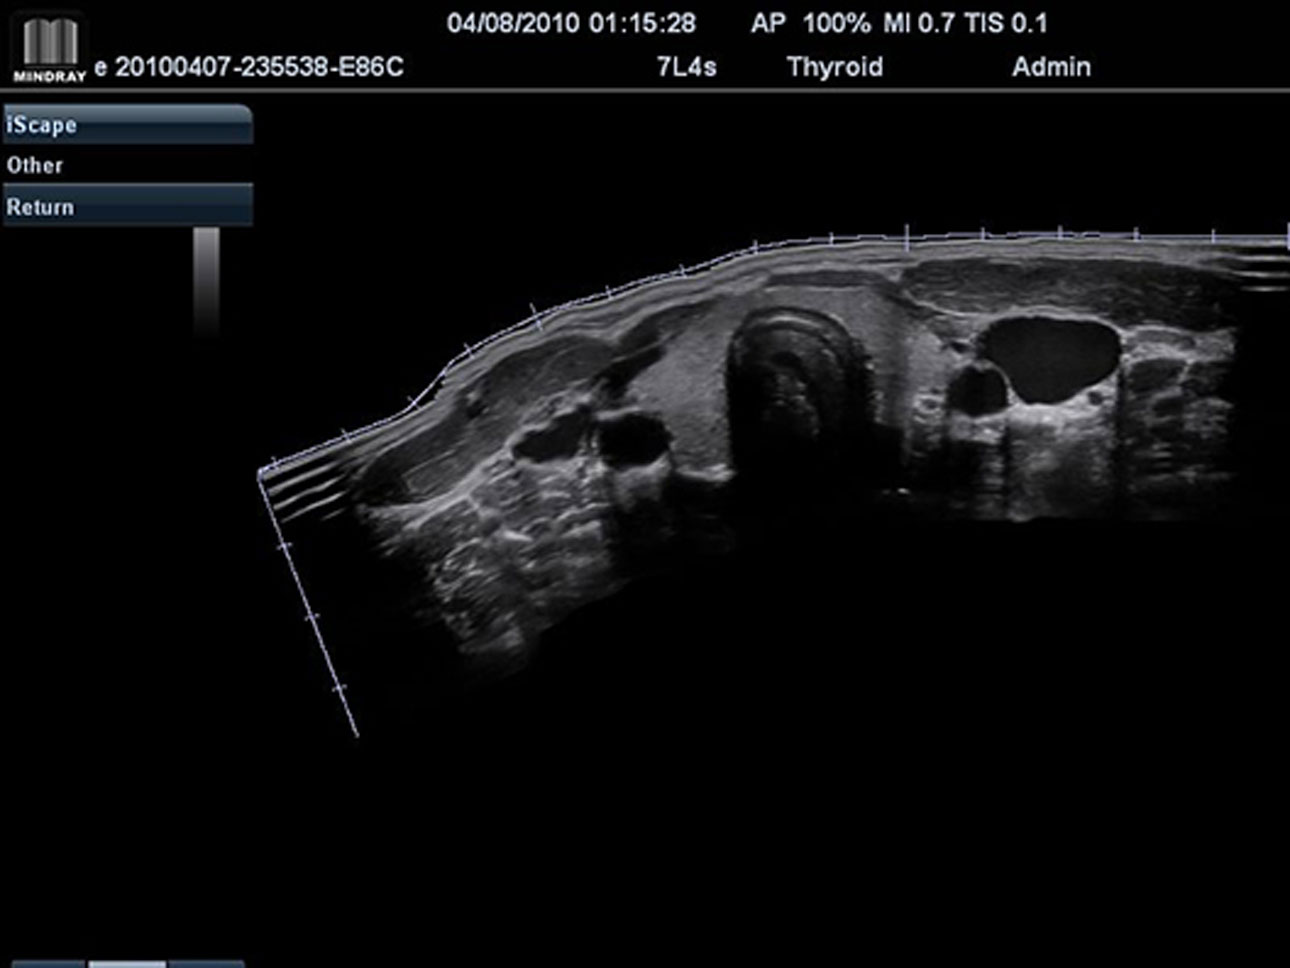

iScapeTM (Real-time Panoramic Imaging)

Get a complete and extended view of the anatomical structure through panoramic imaging, coupled with velocity indication and forward/backward scan ability making scanning much easier, smoother and more controllable.